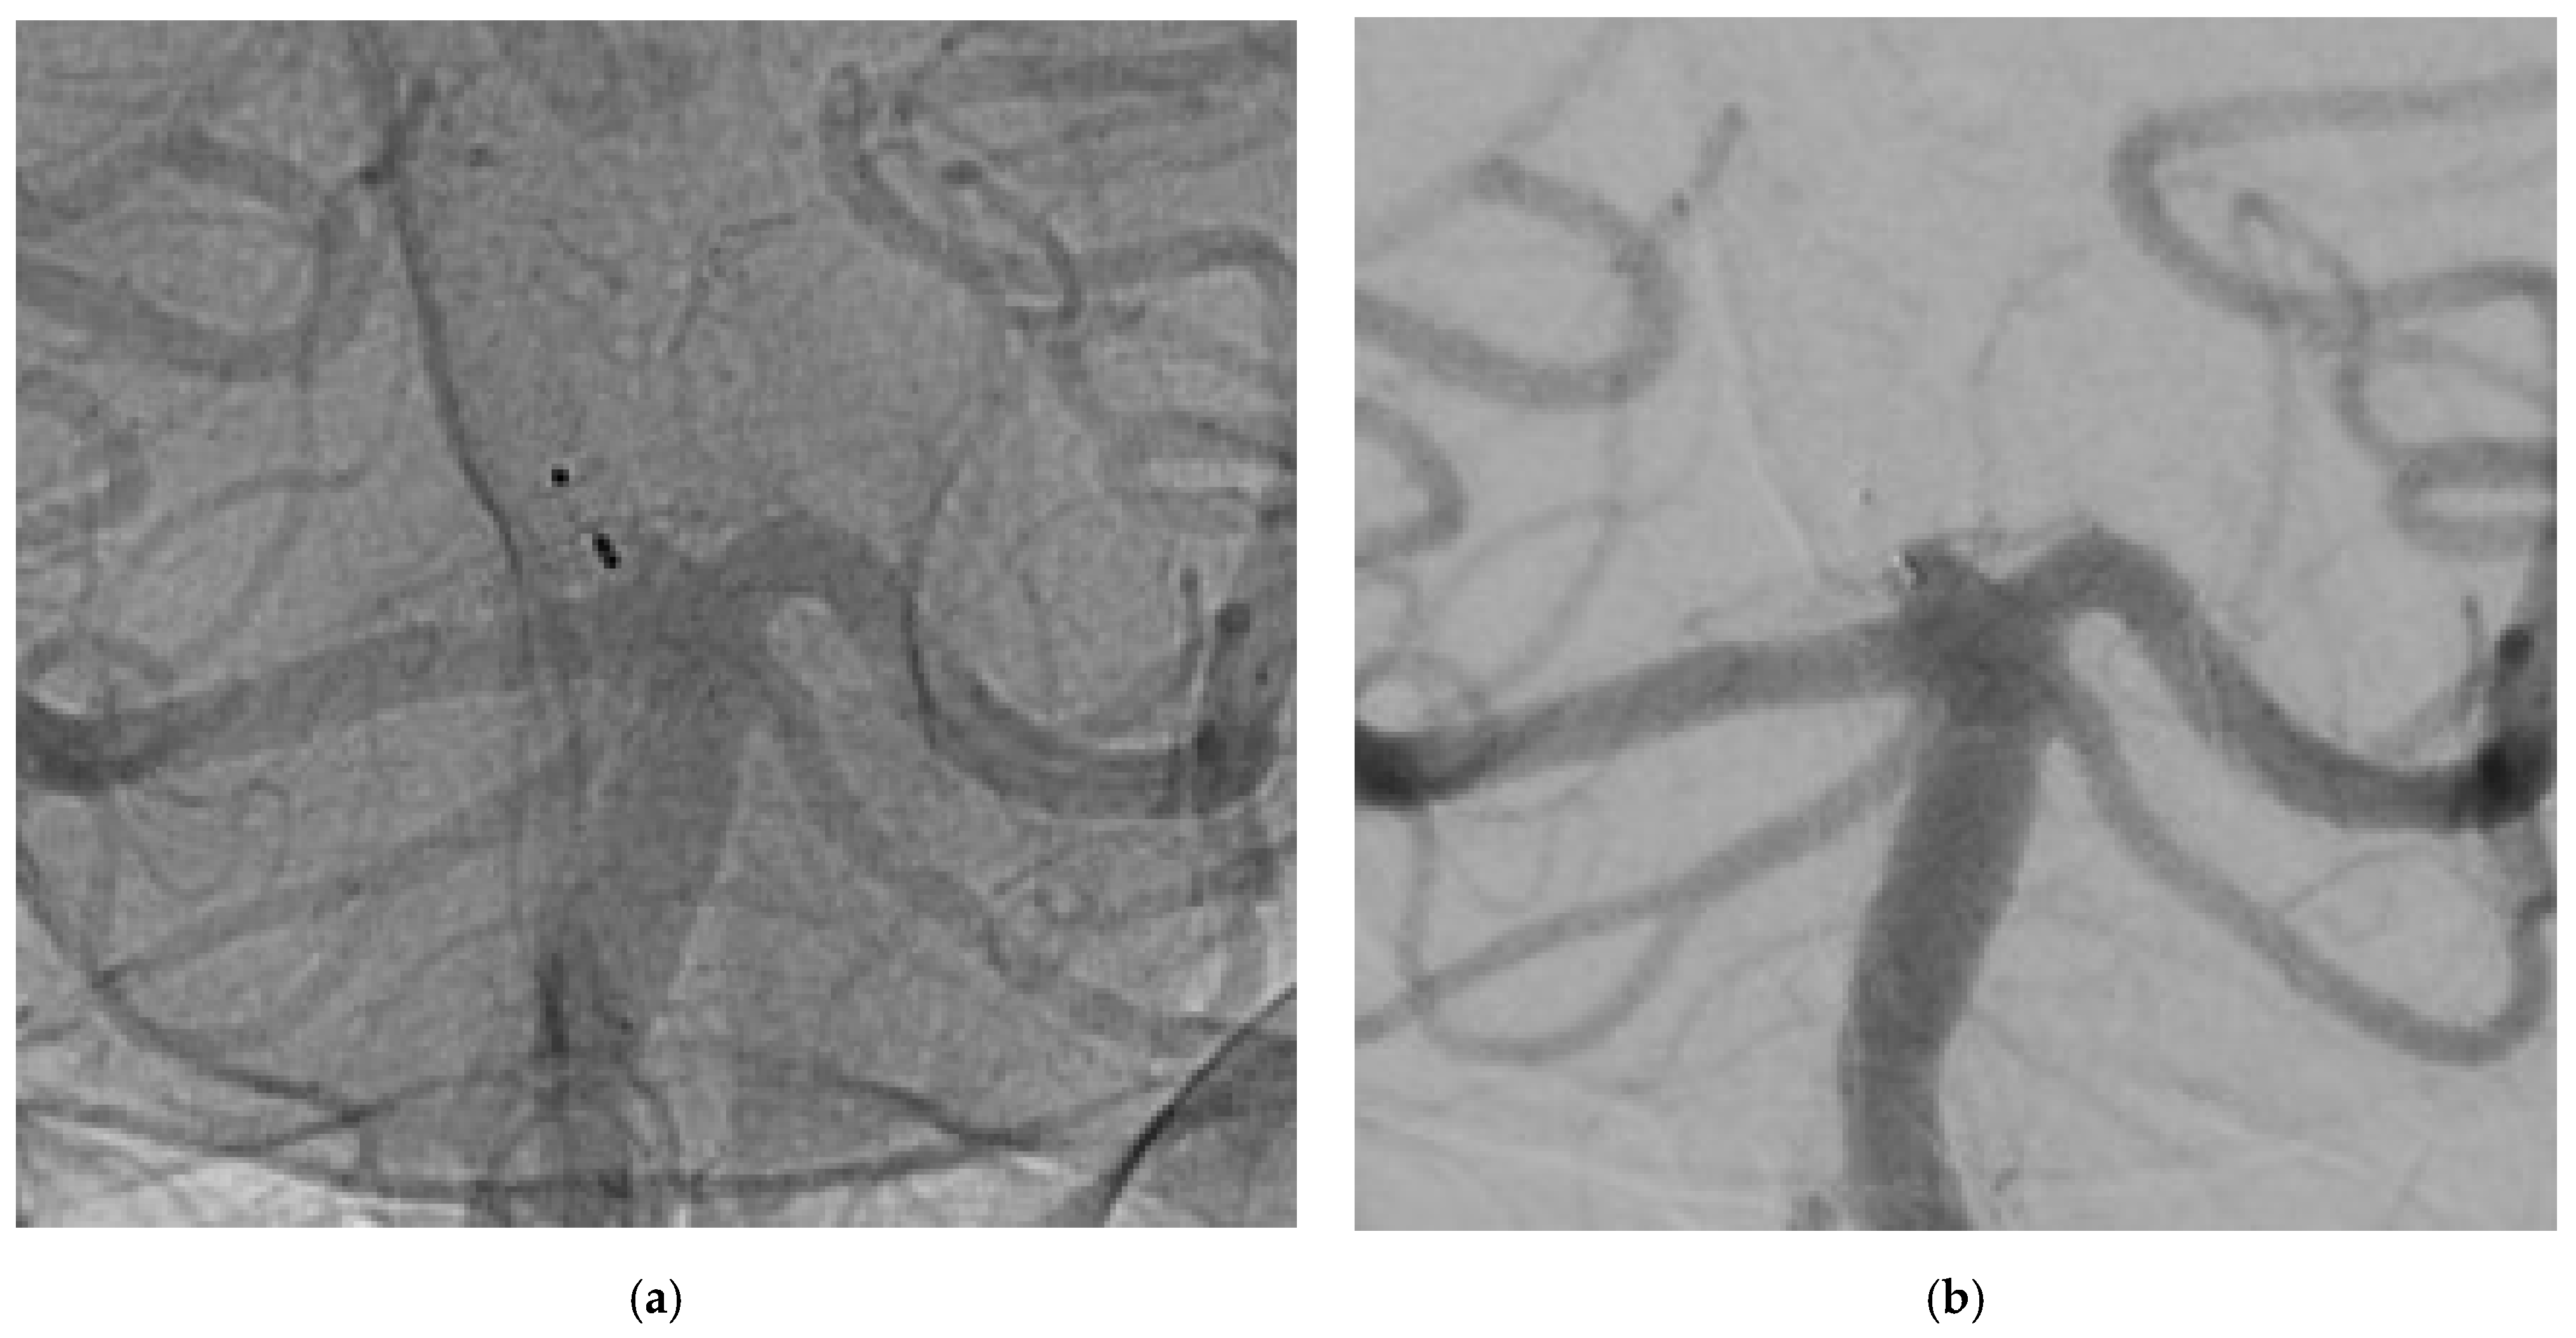

Woven EndoBridge in Wide-Neck Bifurcation Aneurysms: Digital Subtraction Angiography at 3-Year Follow-Up

Angiographic Results